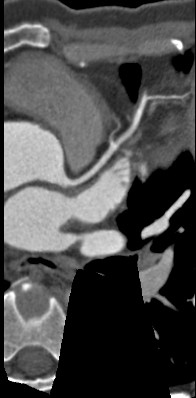

标题: CT24400:患者54岁,心前区不适进行心脏冠脉造影检查。 [打印本页]

标题: CT24400:患者54岁,心前区不适进行心脏冠脉造影检查。

患者54岁,心前区不适进行心脏冠脉造影检查。高手看看有问题没有?

图像很漂亮,好像未见异常